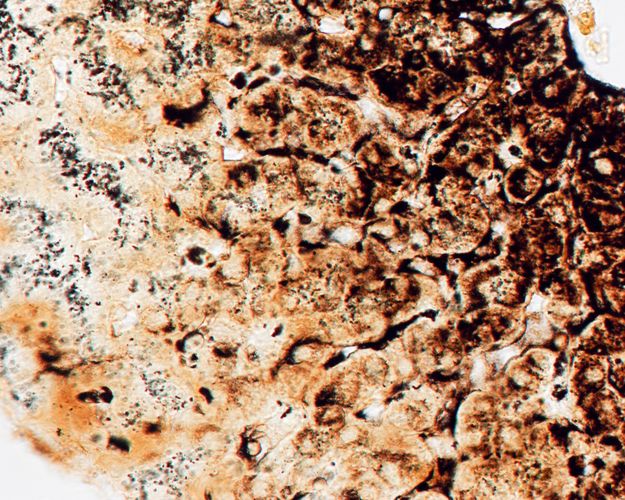

Liver stained with silver to show reticular fibres